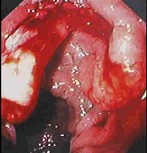

男性,50岁。消瘦、乏力半年,间断性上腹胀痛伴黑便2周。发育正常,体形消瘦,贫血外貌,皮肤无黄染,腹平坦,腹肌软,上腹偏右压痛,肝脾肋缘下未触及。低张气钡双重造影示十二指肠降段肠壁僵硬,蠕动消失,肠腔不规则狭窄。胃镜检查如下图,下列正确的是()。

A:十二指肠腺癌可能大

B:卓-艾综合征可能大

C:该病可导致黄疸

D:该病以中年人多见

E:该病首选手术治疗,无手术指征者可考虑放、化疗